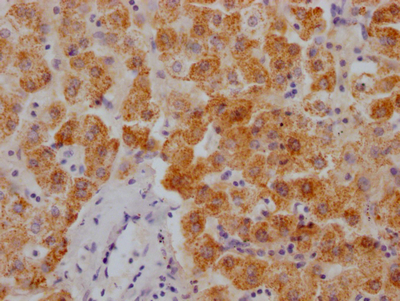

IHC image of CSB-PA03099A0Rb diluted at 1:400 and staining in paraffin-embedded human prostate cancer performed on a Leica BondTM system. After dewaxing and hydration, antigen retrieval was mediated by high pressure in a citrate buffer (pH 6.0). Section was blocked with 10% normal goat serum 30min at RT. Then primary antibody (1% BSA) was incubated at 4°C overnight. The primary is detected by a biotinylated secondary antibody and visualized using an HRP conjugated SP system.